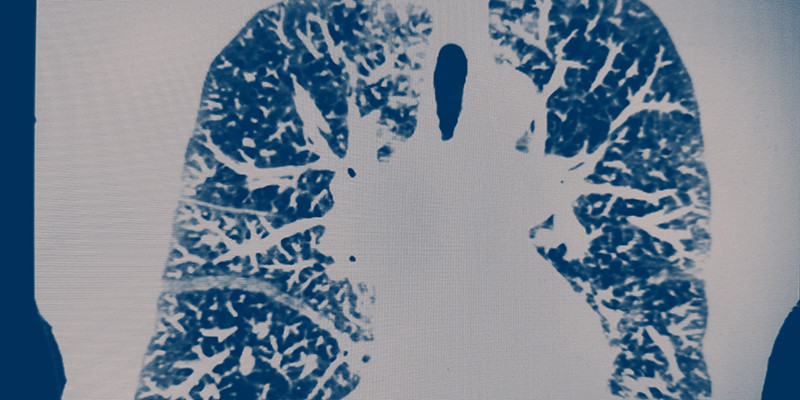

Hart- en vaatziekten zijn veelvoorkomende comorbiditeiten bij patiënten met COPD. Desondanks ontbraken tot voor kort specifieke incidentiecijfers (type hart- en vaatziekten, leeftijd, geslacht). Een Utrechts eerstelijnsonderzoek brengt daarin verandering. Het laat zien dat zowel mannen als vrouwen met COPD op jongere leeftijd vaker hart- en vaatziekten krijgen. Zij hebben ook een driemaal hoger risico op hartfalen.